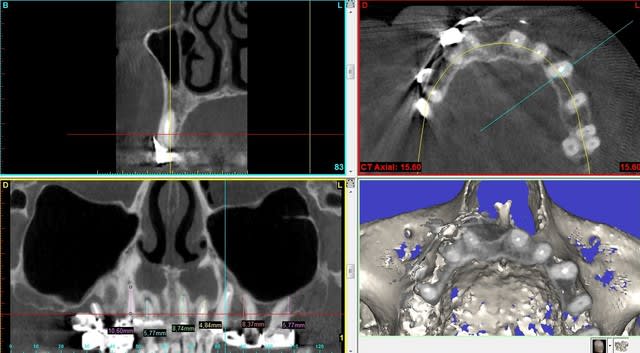

Jeff dans ce cas clinique le plan de traitement a été : empreinte des maxillaires

DVO

Positscan

S.I.A.O

Projet implantaire : extractions, pose de 4 implants, MCI sur 5 implants en récupérant le pilier de l’implant fonctionnel

Validation

Chirurgie

Dans un deuxième temps, les greffes de sinus sont programmées pour la pose de 4 implants

Projet prothétique final : bridge implanto-porté sur 9 implants

Ps : le bridge en pré-op a 15 ans et les implants était bien antérieur.